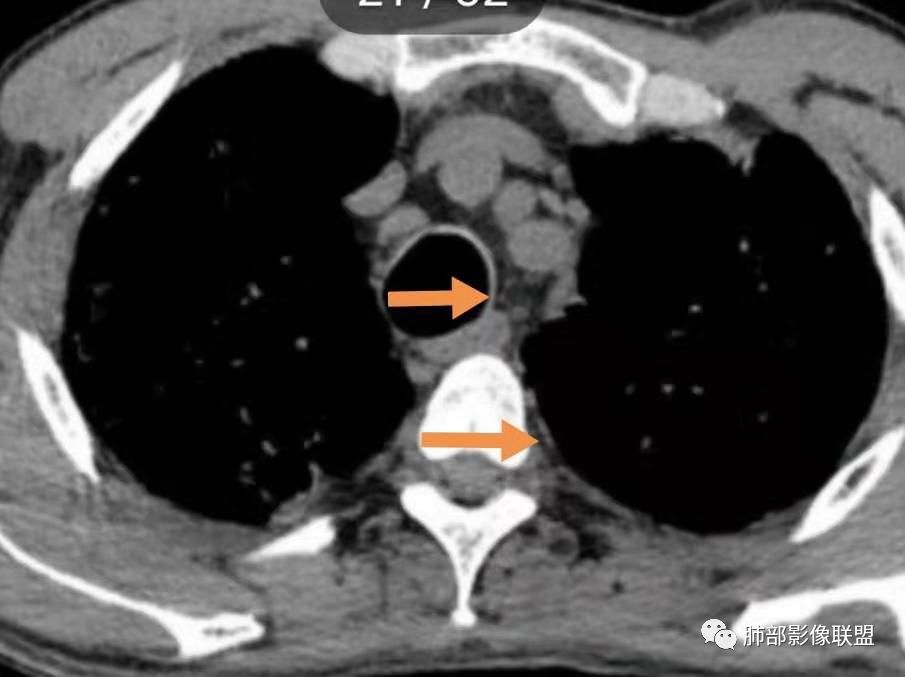

弥漫性间质疾病,还伴心包,胸腔积液的,肺水肿也有可能,但临床不符,没有胸闷气急。

这个病例气管横径=同侧脊柱横径,需考虑气管支气管巨大症?

2. 肺气肿背景(小叶中心性肺气肿);双肺多发病灶整体沿血管支气管束及胸膜下分布,以上叶及下叶背段分布为主,有实变及GGO,边界清楚,有树芽,小叶间隔及中央间质增厚,叶间裂见到多发结节,部分支气管不规则牵拉扩张,提示病灶纤维化明显,结合临床病史,考虑病灶为间质性感染,肺门及纵隔内有钙化淋巴结,小叶间隔结节,考虑淋巴道增值性疾病可能,综合常规要怀疑间质性肺结核。